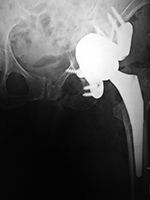

| Unipolar hip hemiarthroplasties (endoprostheses) |

Unipolar hip hemiarthroplasty (endoprosthesis) with a cemented femoral component |

Modular non-cemented unipolar hip hemiarthroplasty (endoprosthesis) |

| These are single piece prostheses press fit into the native acetabulum and the native femur. From Benjamin, 1994 |

Note the collar abutting the femoral calcar. From Benjamin, 1994 |

Note the collar abutting the femoral calcar. |